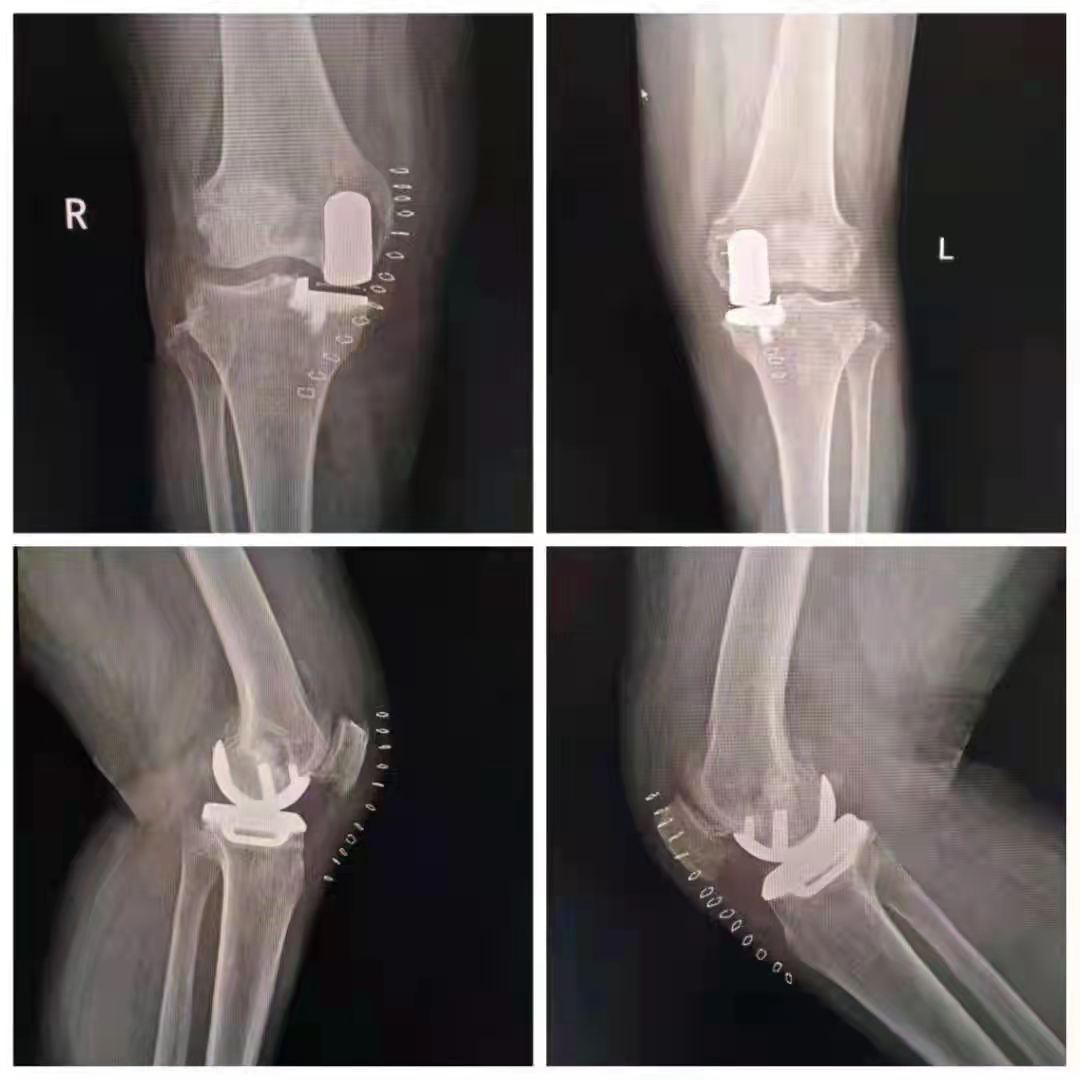

誠德骨科醫(yī)院雙膝單髁置換術(shù)技術(shù)領(lǐng)先

幸運(yùn)的是,王女士慕名來到了山亭誠德骨科醫(yī)院,專家檢查診斷,發(fā)現(xiàn)王女士雙側(cè)膝關(guān)節(jié)內(nèi)側(cè)磨損嚴(yán)重,外側(cè)部分和前后交叉韌帶上好,因此采取雙側(cè)同期部分置換。應(yīng)用牛津單髁活動(dòng)平臺,手術(shù)屬于保膝范疇,保留了好的部分,修補(bǔ)了磨損重的部分,病人感受好,恢復(fù)快,功能好。如果錯(cuò)過這個(gè)修補(bǔ)的時(shí)機(jī),整個(gè)關(guān)節(jié)都磨損了,只能進(jìn)行全膝置換了。

術(shù)后,王女士恢復(fù)很好。疼痛癥狀完全消失,臉上也露出了久違的笑容。